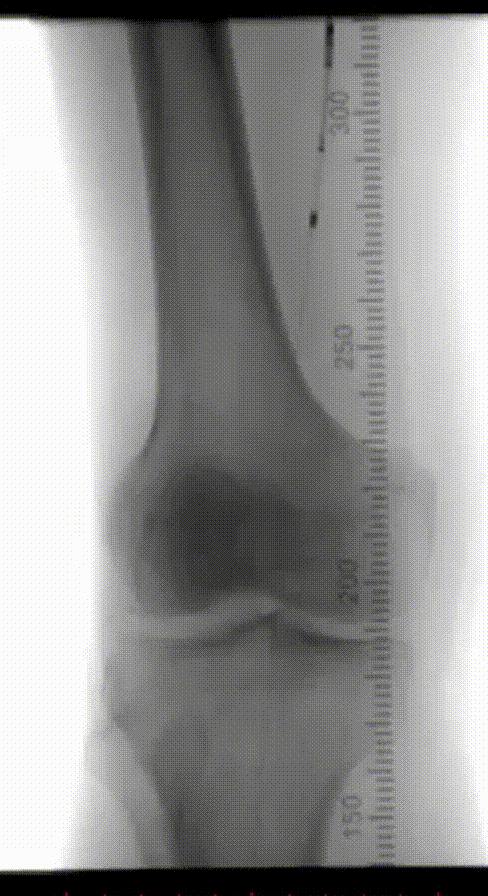

患者为70岁男性,因“右下肢活动后疼痛2月余”入院。

查体:股动脉(左++,右++),腘动脉(左+,右-),胫后动脉(左+,右+),足背动脉(左-,右-)。

既往史:糖尿病、高血压、高脂血症、慢性乙型病毒性肝炎、左肝癌术后右肝复发癌。

辅助检查:ABI(左0.72,右0.56),下肢动脉彩超显示双下肢动脉硬化伴多发斑块,右侧股浅动脉上段闭塞,双侧胫前动脉中下段接近闭塞。CTA提示:腹主动脉粥样硬化,右侧股动脉、双侧胫前动脉中重度狭窄、闭塞,左侧股动脉、双侧腓动脉、胫后动脉轻度狭窄,左侧髂内动脉局限性闭塞。

术前CTA

术前造影